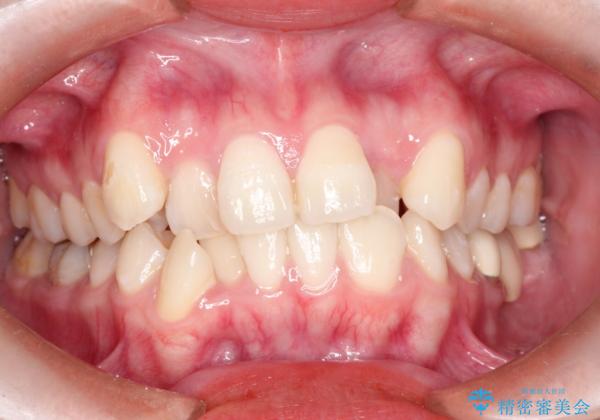

八重歯のワイヤーによる抜歯矯正 矯正治療と並行してセラミック治療も

ブリッジを装着している歯は動かすことができないので、矯正前に除去する必要があることがあります。

今回の場合も、ブリッジを除去して矯正後にセラミックブリッジを装着しました。